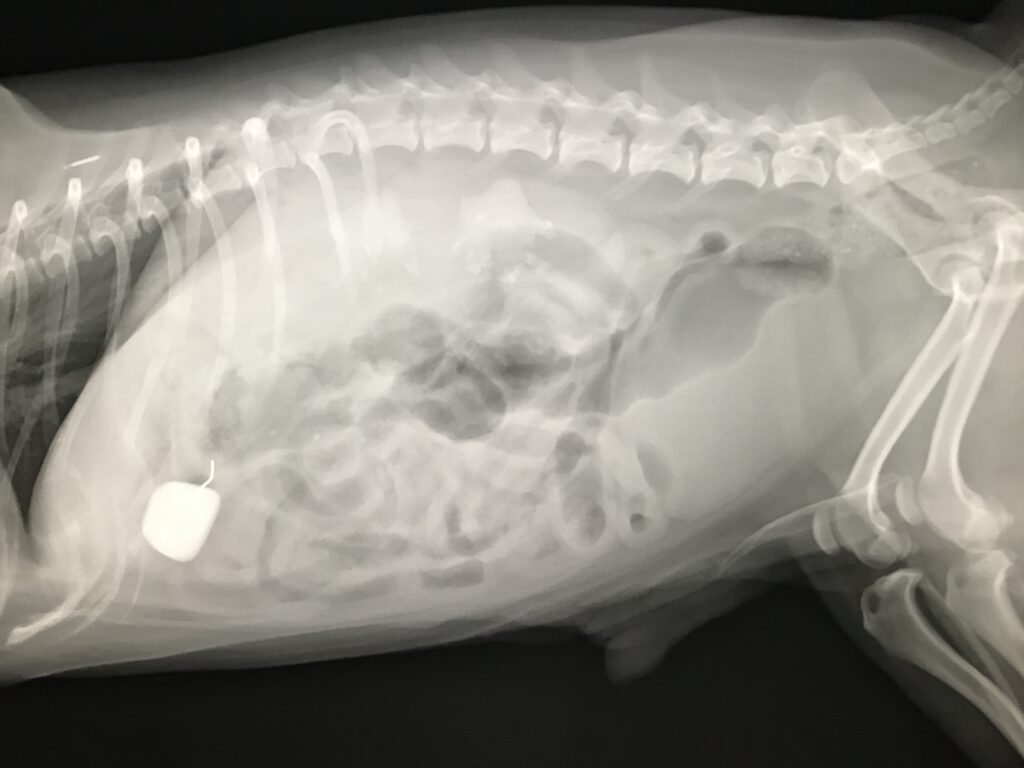

一応レントゲンを撮ると、2cm大の石が写っている・・

この石のせい?よく見ると石と針金状の異物が確認され、その針金が消化管に刺さって痛みを起こしている可能性はあります。ひょっとしたら足腰が痛い可能性もありますが、消化管内異物によって痛みが生じて歩行異常とヨダレが出てるのでは?と判断し、オーナー様に相談の上異物摘出手術を実施しました。